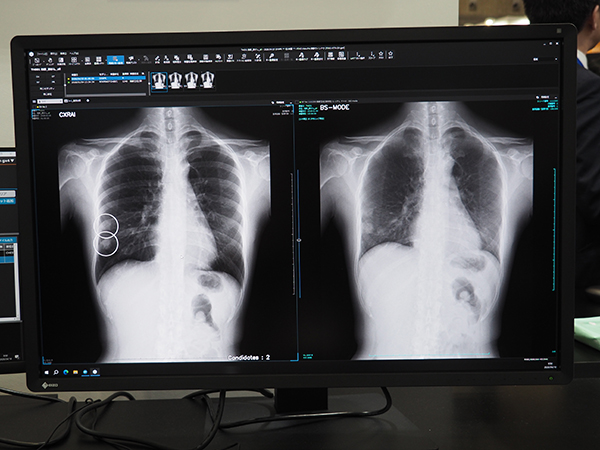

STAT Linkで検出された気胸疑い症例

CXR Finding-i(左)とDDR(右)を併用した病変検出のイメージ。Bone Suppression処理と動画の組み合わせにより,高精度な病変検出が期待できる。